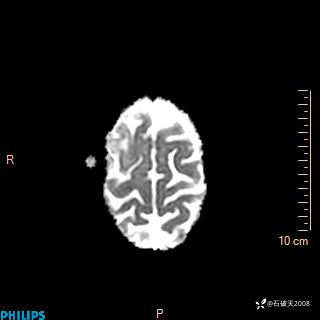

2024.2.21MR

ADC